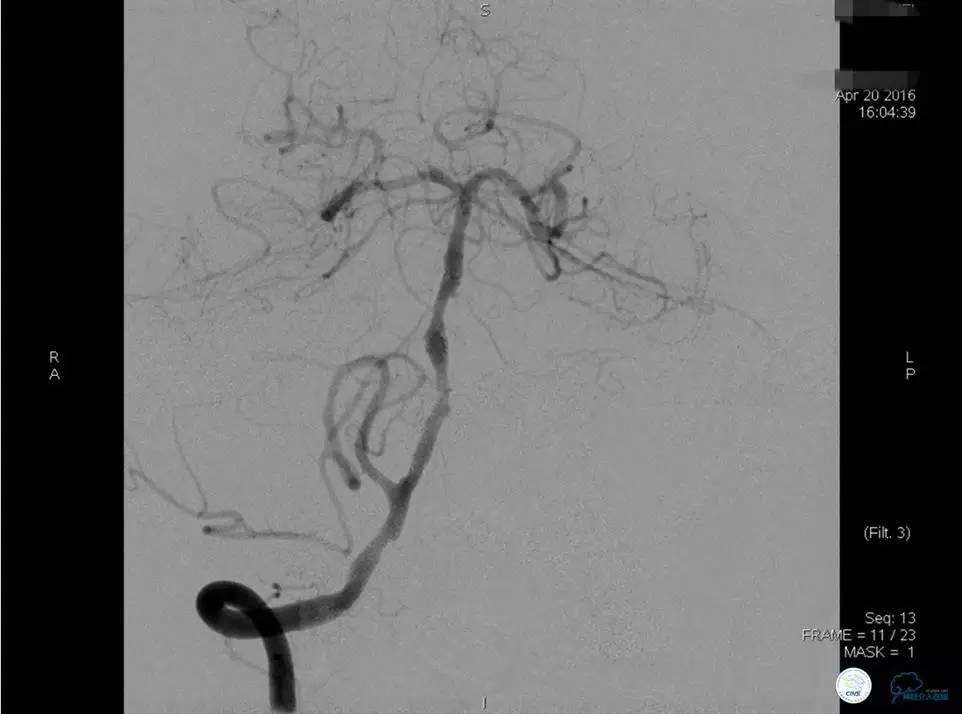

患者:77岁女性,住院后虽然给予药物治疗,仍再次卒中发作。

微导丝穿过狭窄时,有不安全感觉,不很顺畅,拐弯。

经反复尝试,微导丝仍顺利穿过闭塞段。

可见弥漫性长段硬化,选用合适球囊扩张后。

闭塞段很长且成角,置入Solitaire支架,效果好。